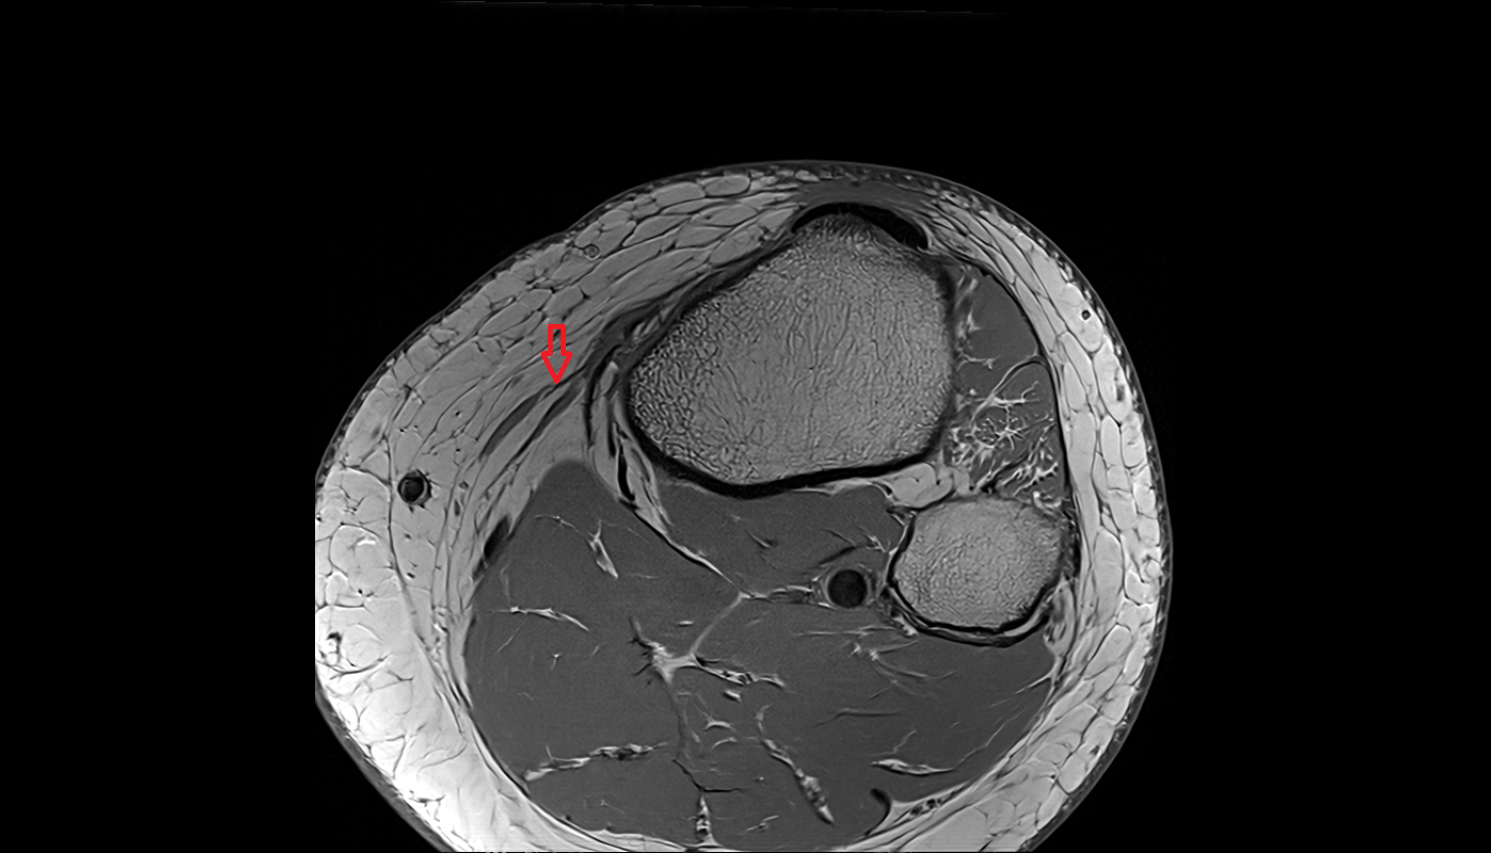

- Knee Joint